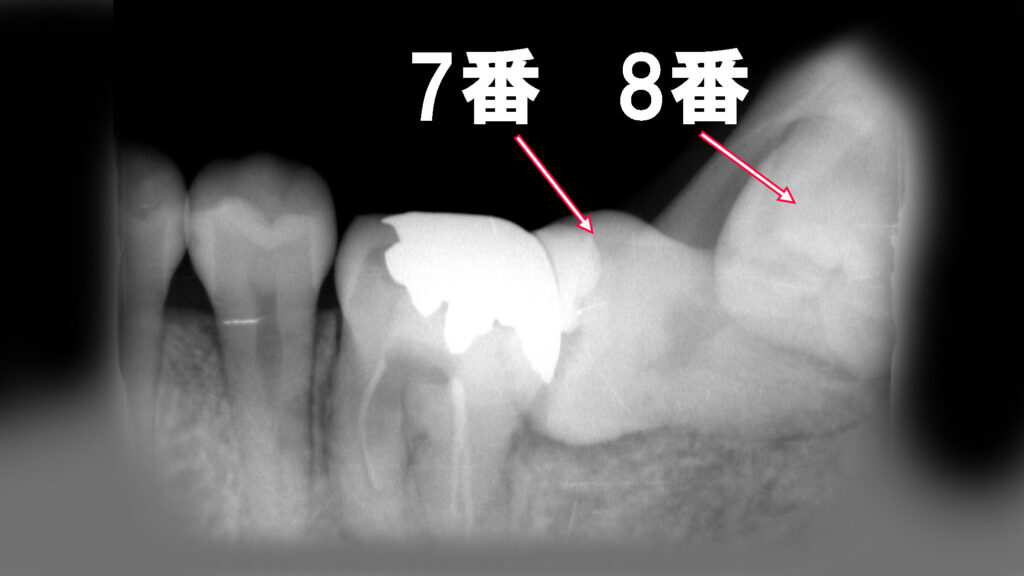

🦷【症例紹介】横向き親知らずが原因で7番の虫歯が悪化したケース

下顎の親知らずのすぐ前にある「7番目の歯」が虫歯になるケースは、実はよく見られます。特に親知らずが斜めに生えていると、手前の歯に様々な悪影響を及ぼすことがあり、その一つが虫歯です(※赤矢印で示した部分)。

この部分の虫歯は非常に見えにくい場所にできるため、自覚症状がなく放置されやすいのが特徴です。レントゲンで確認すると、すでに虫歯が神経まで達しており、痛みが出て初めて気づくというケースも少なくありません。

この口腔内レントゲン写真は、下顎の**第2大臼歯(7番)と第3大臼歯(8番=親知らず)**が水平埋伏していることを示しています。以下に解説します。

🦷 所見の概要

- 7番(第2大臼歯):

歯冠部には金属修復(インレー)が確認されます。

7番の歯軸は強く傾斜しており、8番による圧迫や傾斜の影響が疑われます。 - 8番(第3大臼歯/親知らず):

水平に埋伏しており(水平埋伏智歯)、7番の遠心根(奥側の根)に接触・圧迫している状態です。

歯冠部は骨内に完全に埋まっており、萌出の兆候は見られません。歯根の形成は完了しています。

⚠️ 特徴と臨床的意義

この症例のように、

- 7番・8番ともに水平埋伏しているケースは非常にまれです。

通常は8番のみが水平埋伏することが多く、7番まで傾斜しているのは長期的な圧迫や萌出障害による可能性があります。

臨床的には以下のようなリスクが考えられます:

- 6番遠心部のう蝕(二次カリエス)

- 7番・8番周囲の炎症

- 清掃不良による歯周病リスクの増大

- 将来的な7番の保存困難や8番抜歯時の難症例化

🩺 治療・対応の考え方

- CT撮影による詳細な位置確認

特に下歯槽神経管との距離を把握することが重要です。 - 8番の抜歯を検討

7番への圧迫を解除し、炎症や吸収を予防します。 - 7番の保存治療

根尖や歯根膜に異常がなければ、経過観察または矯正治療、補綴修復を検討。 - 定期的なレントゲンフォロー

再感染や炎症を早期発見するための定期検査が推奨されます。